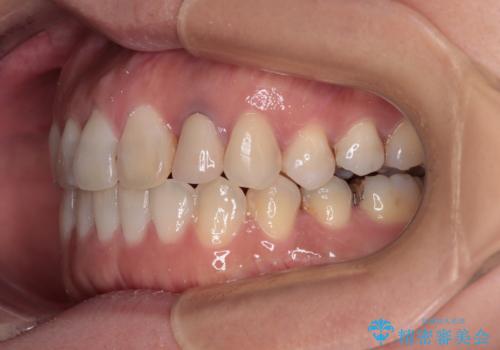

開咬と変色した前歯 インビザライン矯正とオールセラミッククラウン治療

- 前歯の開咬と失活により変色した前歯を気にして来院された患者様です。

開咬の治療は、前歯を閉じるように引っ張り出すよりも、上下臼歯を圧下(骨内にめり込ませる)させることで進める方が長期的に安定した歯列を維持できます。

インビザラインは臼歯の圧下を効果的に行えるため、インビザラインを用いて矯正治療を行うこととしました。

矯正治療が概ね終了した時点で前歯をオールセラミッククラウンにて補綴治療を行い、その後インビザラインにて細かい部分を仕上げていくことしました。